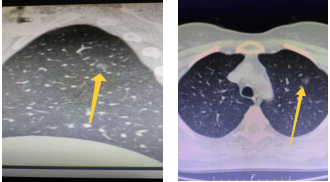

随着健康体检的普及及人们健康意识的提高,越来越多的人在健康查体中查出肺部结节,其中部分患者两侧肺都会有高度疑似早期肺癌的肺结节,传统方案通常是先对病情较严重的一侧肺部手术治疗,待恢复二到三个月后再考虑进行另一侧手术,这对患者无论在身体和心理都带来不小的负担。

我院胸外科全年手术例数全省领先,在先进技术的应用上具有绝对优势。针对双侧肺结节患者,可在胸腔镜下一管双做、同期切除,已成功开展多例,手术创伤小、术后效果好,避免了患者经受二次手术的痛苦和煎熬。

近日,胸外科王述波主任先后为两例患者实施了一管双做早期肺癌根除术,患者一男一女,年龄均40岁出头,体检时发现两肺都有结节,考虑为双侧早期肺癌。因患者为家庭中流砥柱,上有老下有小,这样的查体结果无疑晴天霹雳,心理压力极大。

患者基于对我院胸外科的了解和信任,先后找到王述波主任并充分表达了自己的积极治疗意愿,希望能一次性手术并以最小的创伤同时解决两侧肺结节问题。虽然这样的手术难度大,对手术医师的技术要求较高,是否能同时根除双肺结节,取决于第一侧手术的效果,因为手术过程中,在对一侧肺部手术时患者仅可通过另一侧肺部通气,而且两肺同期经受手术创伤会增加术后发生呼吸功能不全的风险,但王主任对患者身体做了全面评估后,决定实施一管双做手术方案。王述波主任在手术过程中严密观察各项指标,顺利地完成了患者的心愿,一次性切除了患者双侧结节。

王述波主任团队突破传统理念,运用胸腔镜技术一次手术完成两侧早期肺癌根治术,实现了一种新的早期肺癌治疗思路。胸腔镜技术能更大限度减少患者创伤,解剖性肺段切除达到根治两侧早期肺癌的目的,既减少了手术次数,又有效缩短了患者恢复的时间,患者可在一周内恢复出院。